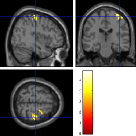

Once the reduced FOV images are available, the proposed pMRI 4D-UWR-SENSE algorithm and its early UWR-SENSE version have been utilized in a final step to reconstruct the full FOV EPI images and compared to the mSENSE Siemens solution. For the wavelet-based regularization, dyadic Symmlet orthonormal wavelet bases [48] associated with filters of length 8 have been used over resolution levels. The reconstructed EPI images then enter in our fMRI study in order to measure the impact of the reconstruction method choice on brain activity detection. Note also that the proposed reconstruction algorithm requires the estimation of the coil sensitivity maps (matrix in Eq. (2)). As proposed in [4], the latter were estimated by dividing the coil-specific images by the module of the Sum Of Squares (SOS) images, which are computed from the specific acquisition of the -space centre (24 lines) before the scans. The same sensitivity map estimation is then used for all the compared methods. Fig. 5 compares the two pMRI reconstruction algorithms to illustrate on axial, coronal and sagittal EPI slices how the mSENSE reconstruction artifacts have been removed using the 4D-UWR-SENSE approach. Reconstructed mSENSE images actually present large artifacts located both at the centre and boundaries of the brain in sensory and cognitive regions (temporal lobes, frontal and motor cortices, …). This results in SNR loss and thus may have a dramatic impact for activation detection in these brain regions. Note that these conclusions are reproducible across subjects although the artifacts may appear on different slices (see red circles in Fig. 5). One can also notice that some residual artifacts still exist in the reconstructed images with our pipeline especially for . Such strong artifacts are only attenuated and not fully removed because of the high level of information loss at .

| mSENSE | 4D-UWR-SENSE | ||

| Axial |  |

|

|

| Coronal | |||

| Sagittal | |||

| Axial |  |

|

|

| Coronal | |||

| Sagittal |